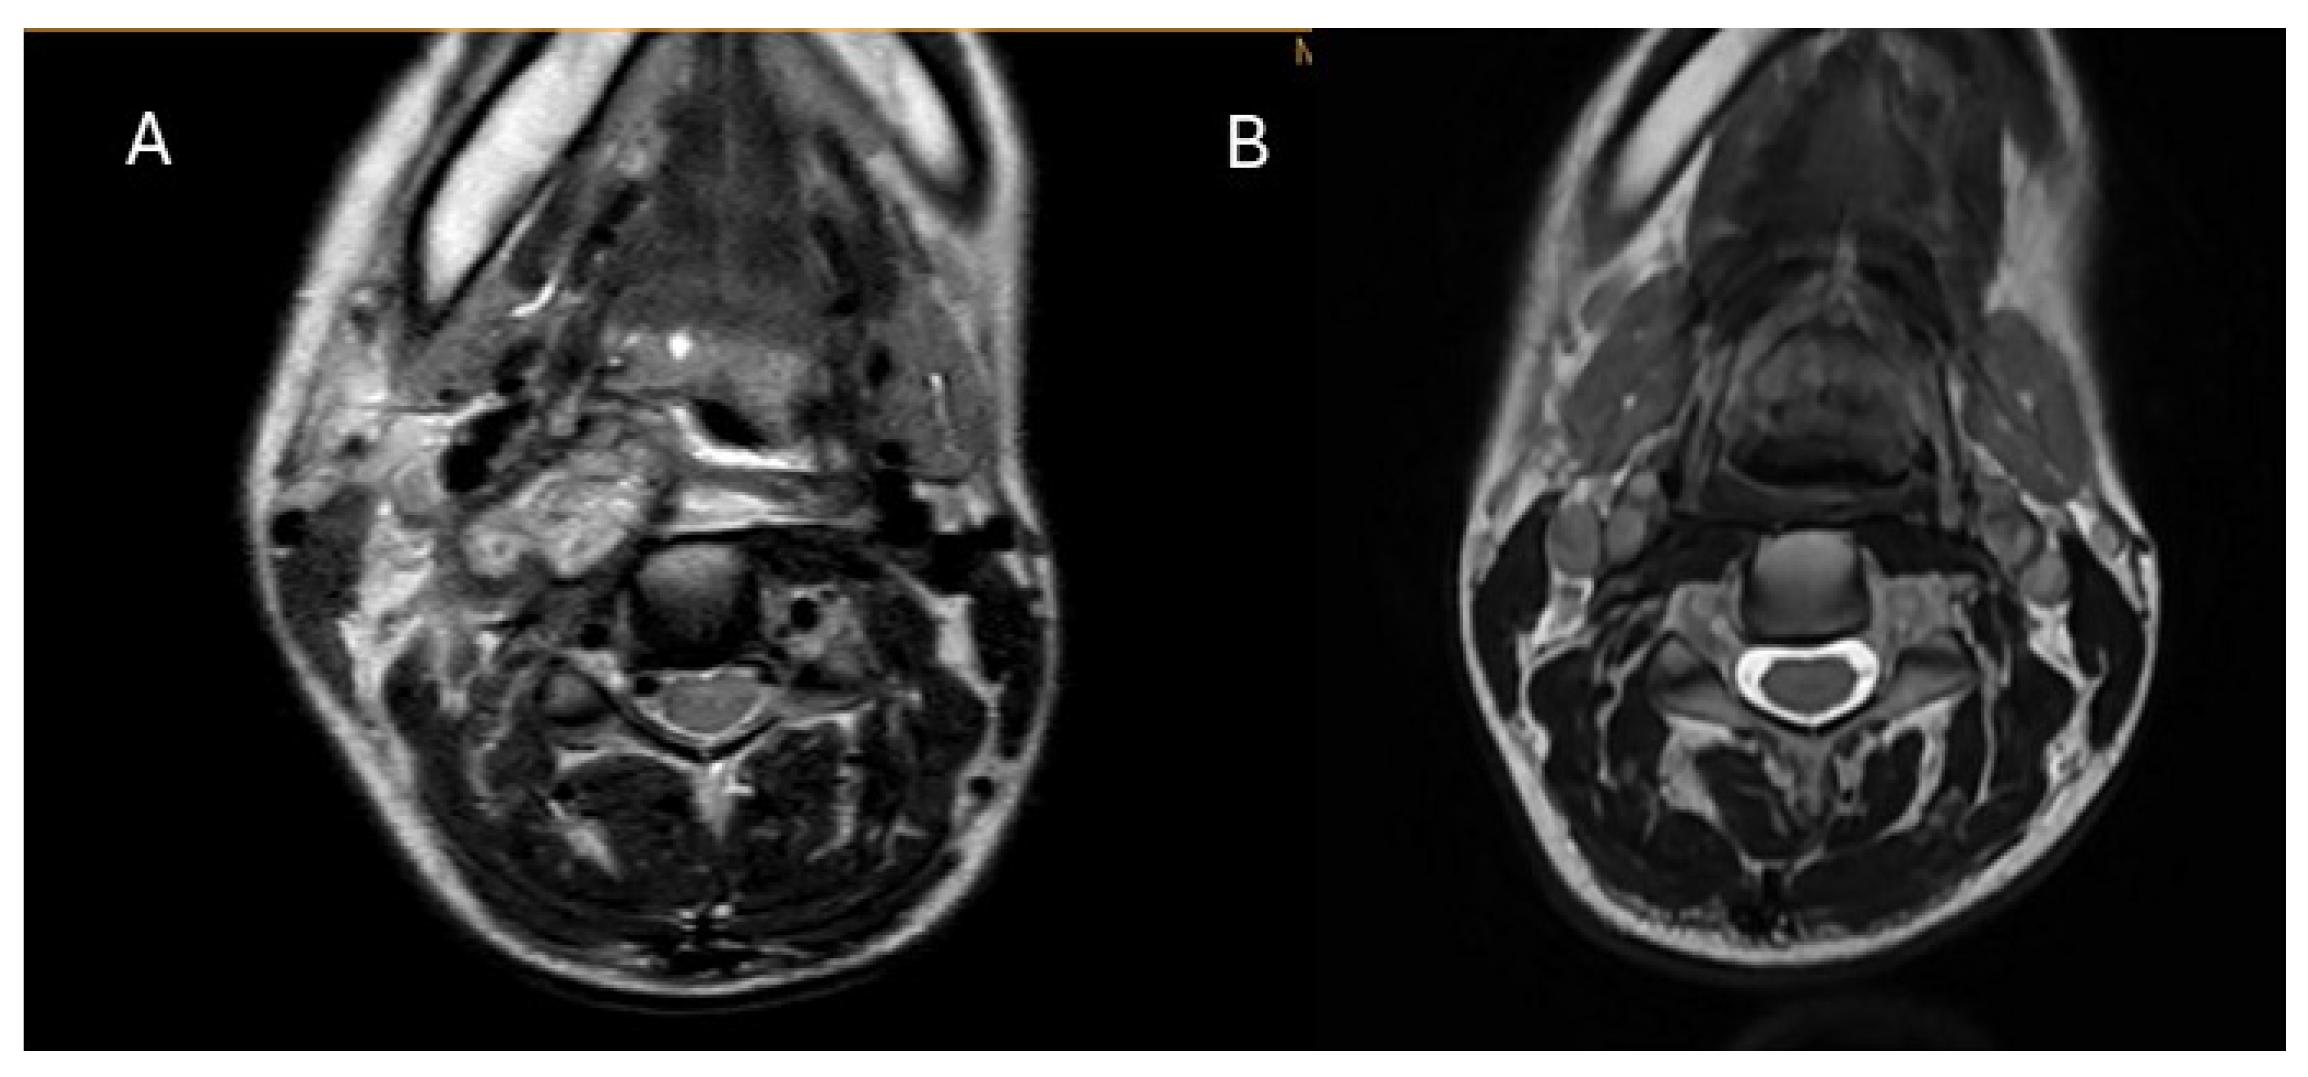

On 6 June 2024, her total white blood cell count was 9.5 × 109/L (normal interval: 3.7–9.3 × 109/L), with 7.5 × 109/L neutrophils and 2.0 × 109/L lymphocytes. Her liver, renal, and thyroid function were all normal, but her erythrocyte sediment rate (ESR) and C-reactive protein (CRP) level were elevated to 112 mm/h (normal interval: 0–31 mm/h) and 12.2 mg/L (normal interval: 0–4.9 mg/L), respectively. MRI was performed on her neck, showing a large irregular infiltration mass over the right side of her neck, with a multi-loculated rim-enhancing area over the right retropharyngeal space, 4.1 × 1.9 × 4.8 cm in size (Figure 1A). The mass extended from the right retropharyngeal space just posterior to the right tonsil to the right carotid space, encasing the right common carotid artery and the internal jugular vein, and further anteriorly to the subcutaneous region of the right anterior neck, with infiltration into the right sternocleidomastoid muscle, at a size of 3.3 × 2.3 × 3.0 cm. A Tru-cut biopsy was performed on 6 June 2024, showing granulation tissue and mixed inflammatory infiltrates with occasional multinucleated giant cells without granulomatous inflammation. The bacterial culture and PCR for Mycobacterium tuberculosis complex were negative. Blood for the interferon-gamma releasing assay was negative. She was given moxifloxacin 400 mg daily for one week but showed no improvement. Blood tests were repeated on 17 June 2024, showing further elevation of ESR to ≥120 mm/h, CRP of 20.1 mg/L, and neutrophil counts of 9.5 × 109/L. In view of the negative microbiological investigation results and the lack of response to antibiotics, an excisional biopsy was performed on 26 June 2024. The histology findings showed acute on chronic inflammation of the skin, with granulation tissue proliferation and fibrosis of the underlying soft tissue. Gram-staining showed a small number of Gram-positive cocci in clusters, but no specimen was sent for culture. Azithromycin was started on 24 June 2024 until 2 July 2024. Wound healing was delayed over the excision site, with persistent whitish chalk-like discharge. The antibiotic was switched to linezolid 600 mg twice daily from 3 to 22 July. A wound swab sample was taken on 5 July 2024, which showed no bacterial growth after 5 days of incubation at 35 °C under both aerobic and anaerobic conditions.

On 22 July 2024, based on the results of the mNGS analysis and the clinical presentation of the patient, the patient was confirmed to have cervical actinomycosis, predisposed due to the usage of steroids for De Quervain thyroiditis. Amoxicillin 2 g twice daily was started on 23 July 2024, and the wounds healed by 29 July 2024. MRI of the neck was performed at regular intervals, and the images from 31 October 2024 showed significant improvement, with complete resolution of the encasement around the right common carotid artery and the right internal jugular vein, and no irregular trans-spatial enhancing lesion noted over the right neck (Figure 1B). The patient recovered completely after 6 months of oral amoxicillin treatment. Informed consent was obtained verbally from the patient for publication of this case.

In this report, we present a case of cervical actinomycosis diagnosed via mNGS of FFPE tissue, which is the most common clinical type of actinomycosis, accounting for approximately 50–60% of all reported cases [5,8]. The diagnosis of cervicofacial actinomycosis can be difficult. Findings in imaging are not specific, as actinomycosis is often confused with malignancy or other chronic cervicofacial infections such as nocardiosis or mycobacterial infections [8]. The gold standard for diagnosing cervical actinomycosis remains histological examination and bacterial culture. In our case, MRI of the neck confirmed the presence of an extensive irregular infiltration mass over the right side of the neck, while the histology and microbiological findings are inconclusive. In light of the lack of response to antibiotics, mNGS was chosen as a last resort to detect any potential pathogens in the specimen.

In general, antibiotic resistance is not a major problem in actinomycosis, and Actinomyces species are usually susceptible to beta-lactam antibiotics [3], with penicillin G and amoxicillin considered the drugs of choice for the treatment of actinomycosis [3,25]. In the research performed by Moghimi et al., which included 19 cases of cervicofacial actinomycosis and 12 studies about cervicofacial actinomycosis via literature search, penicillin or amoxicillin/clavulanic acid were reported as the preferred antibiotic regimens [25]. Therefore, in our case, after confirming the diagnosis of cervical actinomycosis, oral amoxicillin treatment of amoxicillin 2 g twice daily was started, with the wound healed after a week of treatment. MRIs of the neck performed at intervals showed significant improvement after 3 months of treatment, with complete resolution of the encasement around the right common carotid artery and the right internal jugular vein, and no irregular trans-spatial enhancing lesion noted over the right neck. The patient eventually completely recovered after 6 months of oral amoxicillin treatment. This treatment outcome is comparable to those reported in the literature [25].

Figure 1. (A) T2-weighted axial MRI at the level of the mandible. It shows the presence of an irregular infiltration mass over the right side with extension to the retropharyngeal space and carotid space before treatment started. (B) MRI was repeated, and the mass resolved 3 months after starting appropriate treatment.